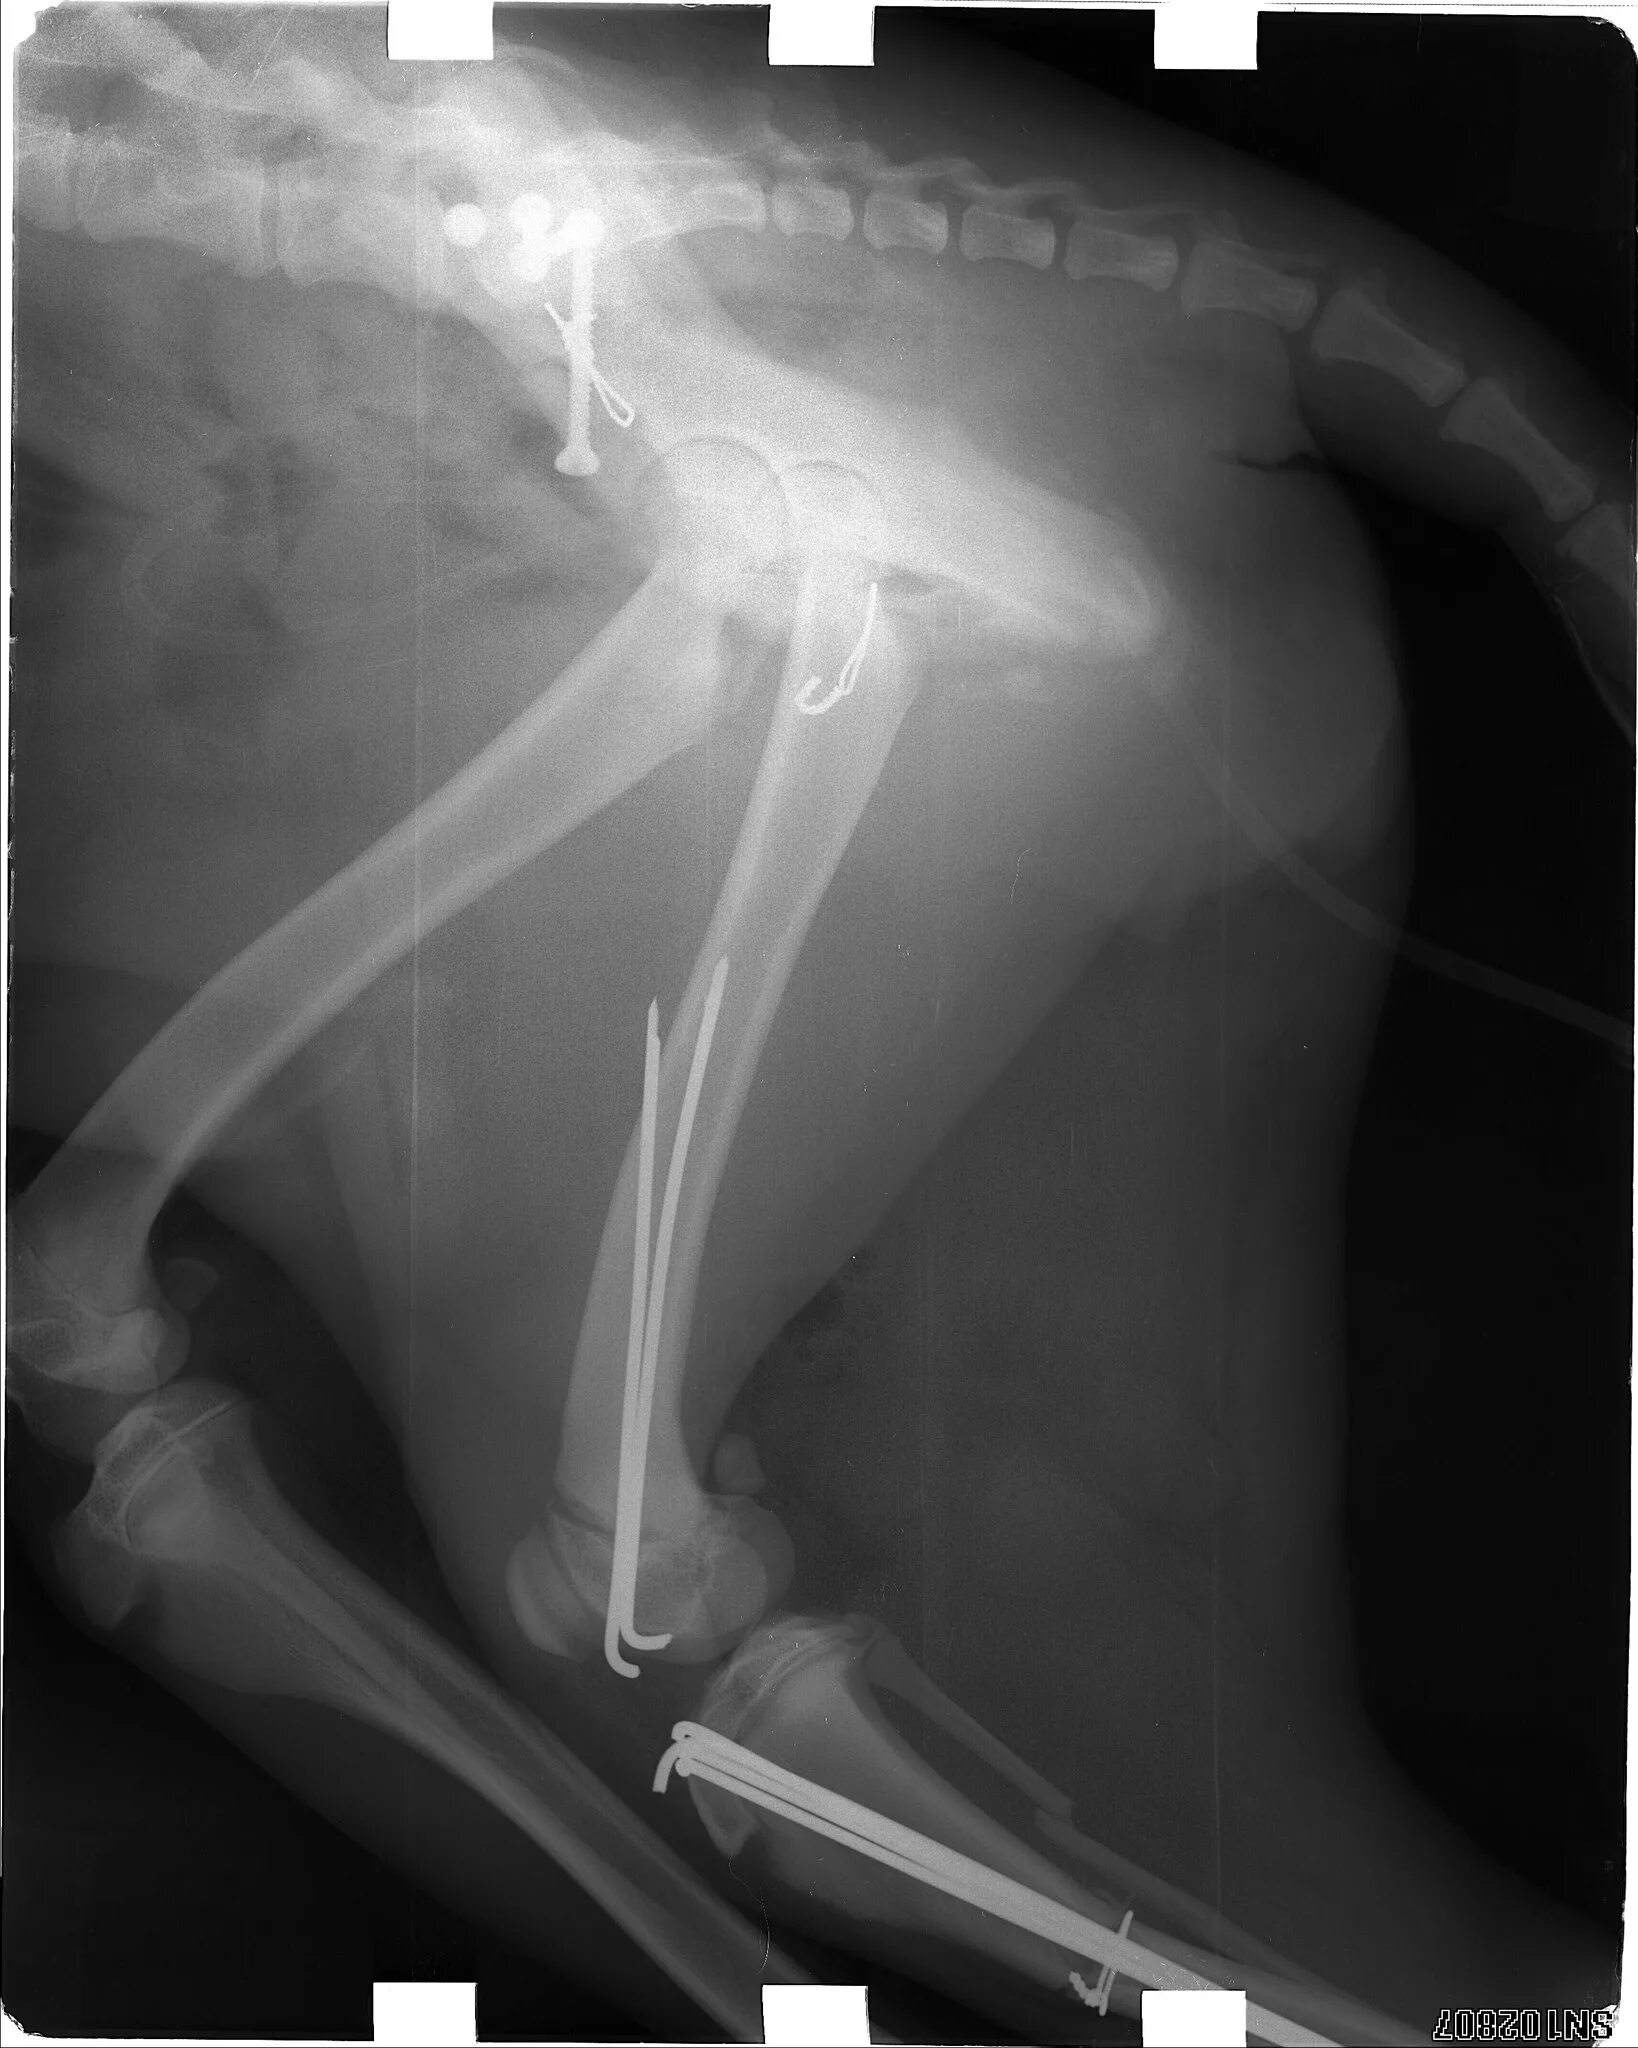

Перелом заднего